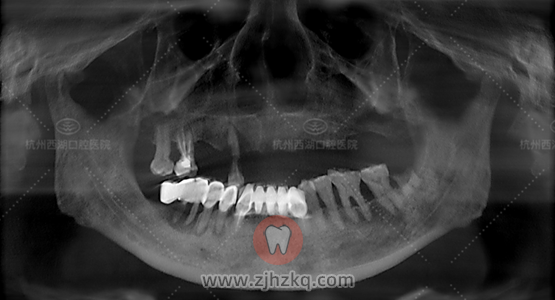

患者自述:上颌剩余4颗,影响日常进食,要求拔除、种植

检查:重度牙周病

医生建议:上颌剩余牙齿拔除,做All-on-N(4—6颗)即刻负重,次日上午手术。

术前CBCT照如下